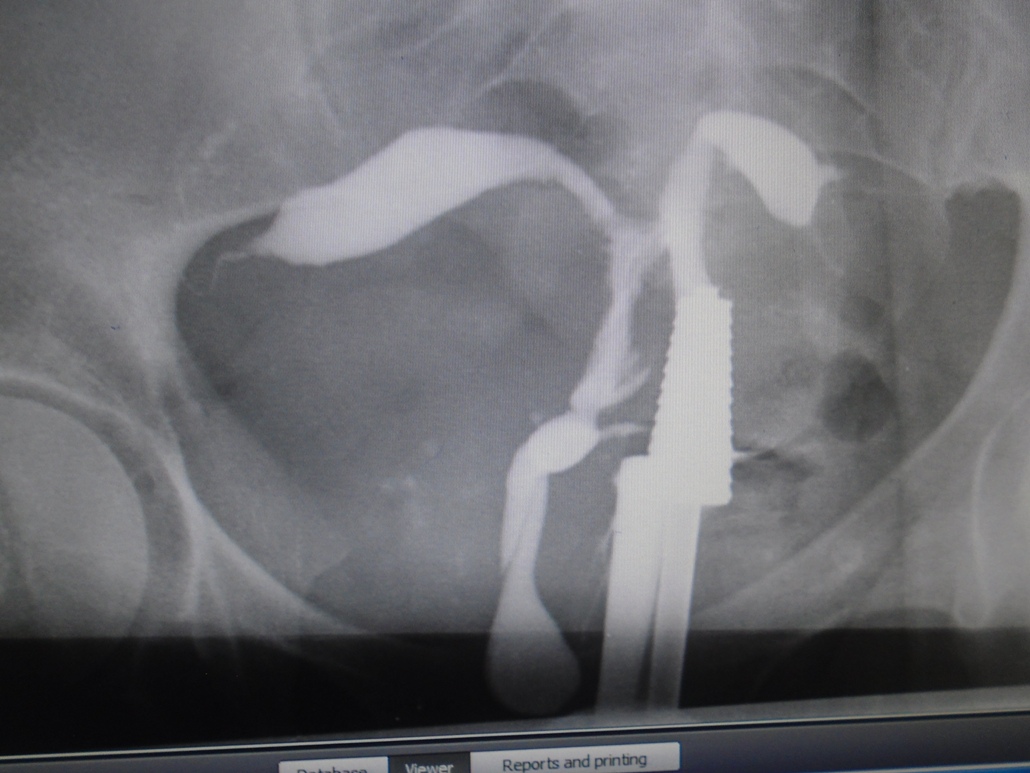

Background: Infertility is a relatively common health challenge in the society with social and psychological consequences. Hysterosalpingogram (HSG) is traditionally used to ascertain some of the causes of infertility. The use of ionizing radiation and contrast media injection with the possibility of complications, make new imaging modalities preferable, especially when in-vitro fertilization is being considered as a management option.

Objective: To describe the pattern of the cervical, uterine, tubal and adnexial abnormalities causing infertility as detected by HSG in a tertiary health care institution, and demonstrate the prospects of retaining Hysterosalpingography in the investigation of female infertility.

Methods: The HSG and reports of 124 patients referred to the Radiology Department of a tertiary health facility between January, 2013 and June, 2014, at a tertiary healthcare institution, were reviewed for abnormalities in the cervix, uterus, the fallopian tubes and adnexial structures.

Results: Secondary infertility was the commonest indication for the procedure among in 66 of the 124 HSG reviewed. Pathologies in the cervix were found in 66 (51.6%) cases, of which the most frequent abnormality was cervical fibrosis in 59.4% (36/66) cases.  Uterine abnormalities were found in 71.7% (89/124) cases, with uterine fibroid occurring in 82% (73/89) of these cases. Pathologies in the Fallopian tube occurred in 68 (54.8%) cases, with bilaterally blocked tubes occurring most frequently in 32.4% (22/68). Twenty-seven of the 68 cases (39.7%) with tubal abnormalities were aged 20-29 years.

Conclusion:  Secondary infertility was the commonest indication for HSG in the study, while uterine fibroid, cervical fibrosis and bilaterally blocked tubes were the most prominent findings in descending order of frequency. Therefore, caution should be exercised in managing pelvic infections, inflammations, diagnostic dilation and curettage and post-abortal and post-surgical periods in order to reduce the risk of fibrosis.